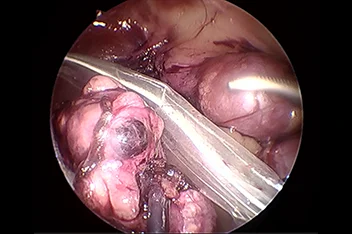

1. 복강경 수술

간단한 중성화부터 부신절제, 간엽절제, 담낭절제 등 고난도 수술까지 적용 가능하며, 대형견에서 특히 효과적입니다.

복강경

기존의 개복수술은 충분한 노출을 위하여 복부의 피부와 복벽 근육을 길게 절개해야 합니다.

하지만 복강경을 이용하면 보통 3mm-10mm 직경의 포트를 통해 복강 내에 이산화탄소를 주입하여 공간을 만들고,

카메라를 통해 더 뚜렷하게 시각화할 수 있고 지혈 기구를 통해 장기들을 안전하게 분리하여 절제할 수 있습니다.

복강경의 경우 대형견에서 그 장점이 뚜렷하며 현재는 소형견, 고양이에서도 이러한 장점 때문에 최소 침습 수술을 진행하게 됩니다.

본원에서는 간단한 중성화나 조직생검 외에도 부신절제술, 담낭절제술, 신장절제술, 비장절제술, 간엽절제술 등을 포함한

고난도 수술도 실시합니다.

복강경신장절제술

복강경부신절제술

복강경담낭절제술

* 리본동물의료센터 케이스 사진으로 무단 복제 및 도용을 금지합니다.